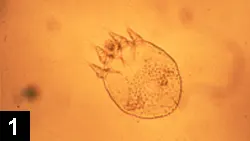

Infestation in dogs is caused by Sarcoptes scabiei var. canis. Mites are small (200 to 400µm) and oval, with two pairs of anterior legs and two pairs of rudimentary hind legs that do not extend beyond the body (Figure 1).